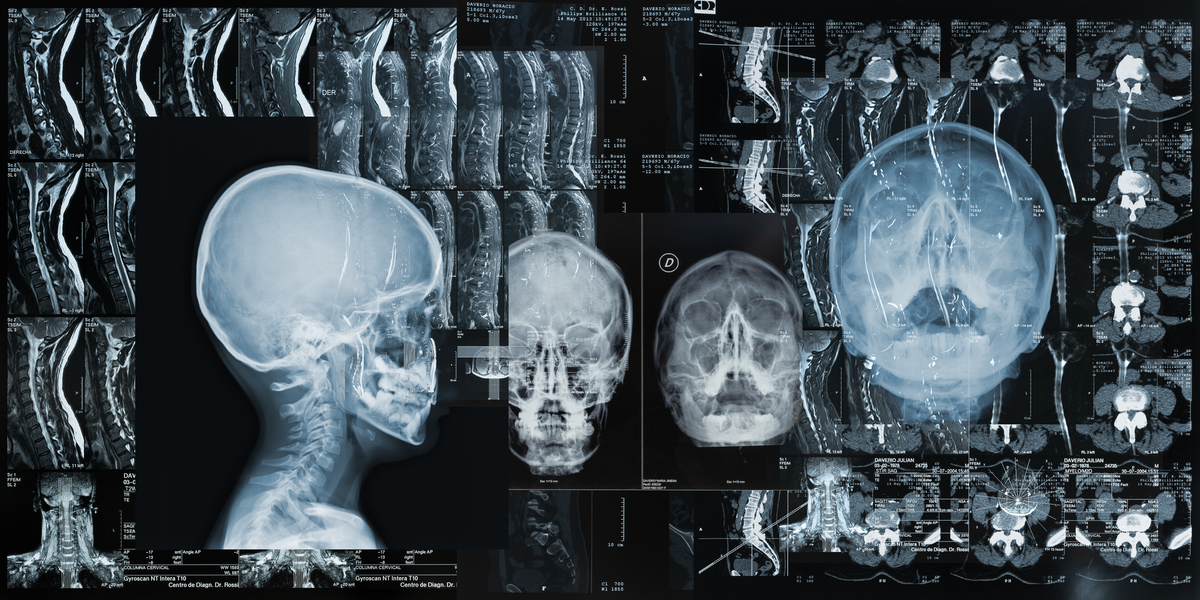

“We try to get a status assessment. See where they are at, how they are feeling, and what the injury is basically telling me. We’ll go through signs and symptoms and then I’ll do my special tests that kind of point me towards what the injury is or what I think it is,” noted Diers. “From there, if they need to see a doctor, I connect with them. If I think it's something I can handle myself, then we just start a rehab plan.”